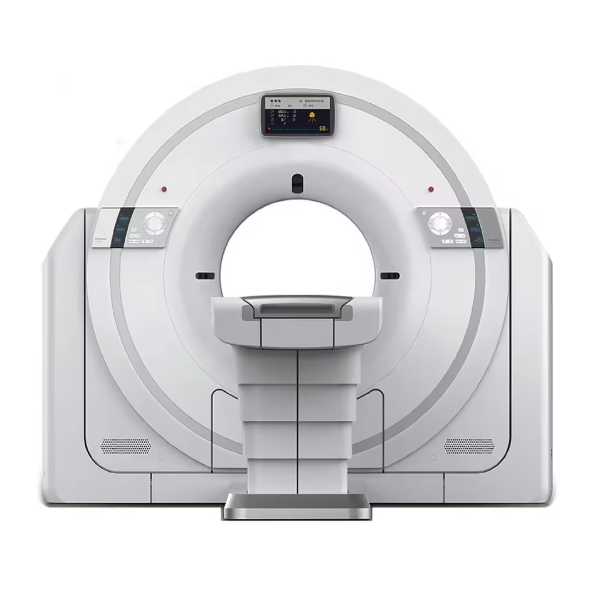

CT Scan

CT Scan Machine – Advanced Imaging Technology for Accurate Diagnosis

A CT Scan (Computed Tomography Scan) is one of the most powerful

medical imaging tools used in hospitals, diagnostic centers, and clinics worldwide.

Designed to provide clear and detailed cross-sectional images of the body,

a CT Scan machine plays a vital role in diagnosing diseases, monitoring conditions, and guiding treatment plans.

What is a CT Scan?

A CT Scan is an advanced imaging procedure that uses X-ray technology and computer processing

to create highly detailed images of bones, organs, blood vessels, and tissues.

Unlike standard X-rays, CT scans offer 3D imaging for accurate diagnosis,

making them essential in modern healthcare.

Key Features

High-resolution 3D imaging.

Low radiation dose technology.

Fast scanning for emergency care.

User-friendly software interface.

Long-lasting reliability and efficiency.